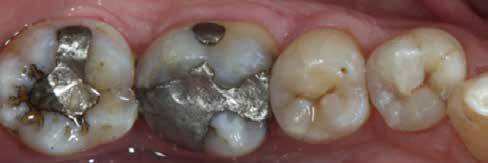

3. ábra: A preparálás, a bondozás és a kompozit felvitele után. (Megjegyzés: némi kompozit túlfolyás látható a mesiális doboz axiális falain).

4. ábra: A durva finírozás után a restauráció pereme sima és anatómiailag is megfelelő.